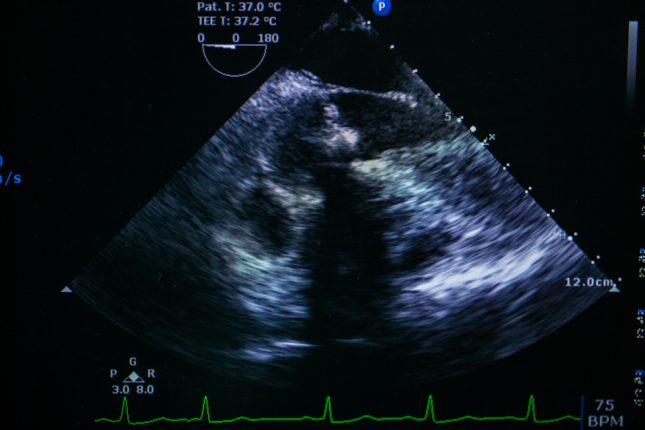

החוקרים גייסו חולי דלקת כבד נגיפית הסובלים מתלסמיה לצורך הערכה פרוספקטיבית. מדי יום ניתנו לחולים כדורים במינון של 90 מ"ג לדיפסוויר (או 60 מ"ג דקלטסוויר) בשילוב עם 400 מ"ג סופוסבוויר (עם/ללא ריבווירין). הכדורים ניתנו בהתאם להנחיות מערך ההפטיטיס האיראני. מומחה באקו-לב אסף את הממצאים של כלל המטופלים לפני ולאחר הטיפול. המטופלים היו תחת מעקב אחר כל אירוע לבבי במהלך 12 השבועות לאחר תום הטיפול.

32 מטופלים שגילם הממוצע היה 24.2 עם סטיית תקן של 6.4 עברו הערכה במהלך המחקר. כל המטופלים הראו תגובה וירולוגית ממושכת בשבוע ה12 לאחר תום הטיפול. המדדים הבאים במטופלים עלו משמעותית לאחר סיום הטיפול: קוטר (3.0 לעומת 3.24; p=0.003) ונפח (33.8 לעומת 43.6; p=0.001) של החדר בסוף הסיסטולה, עיבור אורכי כללי (Global longitudinal strain – GLS)י– (22.0- לעומת 20.6-; p=0.046), עיבור אורכי ממוצע (21.4- לעומת 20.3-; p=0.048) וגודל החדר הימני (3.12 לעומת 3.31; p=0.012).

החוקרים ציינו כי שינוים במדדים הנ"ל לא היו בקורלציה עם עומס הברזל בשריר הלב של המטופלים. החוקרים לא מצאו הבדלים משמעותיים במדדי אקו אחרים (p>0.05) לפני ולאחר הטיפול.

מסקנת החוקרים היתה כי טיפול מבוסס סופוסבוויר בדלקת הכבד הנגיפית היה בטיחותי עבור המטופלים הנ"ל. מקטע הפליטה (ejection fraction) נותר ללא שינוי במטופלים שהשתתפו במחקר. מכאן שהערכה ממוקדת על ידי אקו-לב הינה, לדעת החוקרים, מומלצת עבור חולי הפטיטיס עם תלסמיה הנוטלים טיפול אנטי ויראלי ישיר והם בעלי היסטוריה של פגמים לבביים, עומס ברזל בשריר הלב וכן בכל מקרה של תופעות לוואי הקשורות ללב במהלך הטיפול.